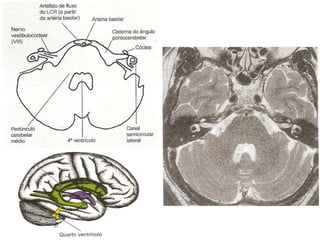

Ressonância Magnética do Crânio

• Sistema de obtenção de

imagens é mais sensível à

natureza molecular dos tecidos;

• Alta densidade tissular não

resulta em resolução de

contraste.

   Doenças da substância branca;

   Neoplasias;

   Doenças infecciosas;

   Distúrbios hemorrágicos;

   Distúrbios isquêmicos.